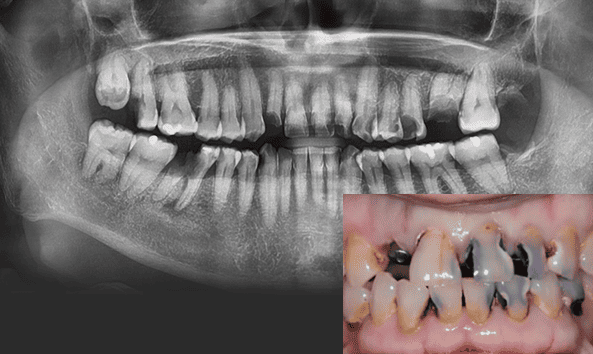

충치는 흔한 질환이지만 스스로 회복되지 않습니다. 통증이 있어도 치료를 미루다 보면 적절한 시기를 놓쳐 더 많은 비용과 시간이 들 수 있습니다. 정기적인 구강검진으로 문제를 조기에 발견하고 신속히 치료받는 것이 건강을 지키는 가장 현명한 방법입니다.

단계별 충치치료를 통해

최선의 진료를 찾고

자연치아를 최대한 보존합니다.

법랑질 충치

치아 겉면인

법랑질의 충치로 통증이 거의 없습니다.레진치료

상아질 충치

법랑질 안쪽에 있는 상아질까지 충치가 진행되어 뜨겁거나 차가운 음식을 먹으면 시린 증상이 나타납니다.

인레이

치수염 충치

상아질 안쪽 신경까지 염증이 진행되어 극심한 통증으로 참기 어려운

정도가 됩니다.신경치료 + 크라운

치주 괴사

치아 내부에 있는 조직이 괴사되고, 뿌리 주변의

염증으로 인하여 뼈가 점차 소실됩니다.발치 + 임플란트